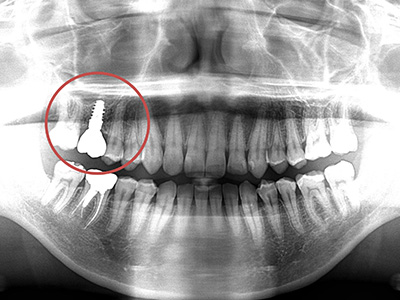

Feature02

見た目も噛み心地も妥協しない

「補綴主導型インプラント」

一切妥協しないインプラント

最終的な被せ物(補綴)の理想的な形・位置から逆算し、インプラントを噛み心地と見た目に最適な位置に設計・埋入します。

技工士と院長が共同で設計し、その中心に正確にインプラントを配置。自然な見た目と快適な噛み心地の両立が可能になります。